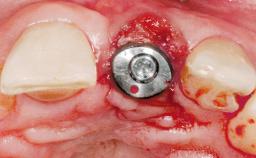

Immediate Flapless Placement of an Implant in a Maxillary Left Central Incisor Site

A 29-year-old female patient presented for treatment to replace the upper left central incisor tooth with an implant- supported restoration. The tooth had been intermittently symptomatic for the previous 12 months. The tooth had originally suffered trauma about 15 years previously. Several endodontic treatments had been performed, including an apicectomy procedure to retain the tooth. The patient was healthy and a non-smoker. She had reasonable expectations in regard to esthetic outcomes and the risk of marginal tissue recession following treatment. At medium smile, the gingival margins of the upper teeth were visible, with a display of 3 to 4 mm of the gingival margins. Gingival recession of tooth 21 and a discrepancy in the gingival levels between teeth 11 and 21 was observable during normal speech and smile.

Placement Protocol | Immediate implant placement |

Socket Morphology | Single-root socket |

Socket Integrity | Damage to one or more bone walls |